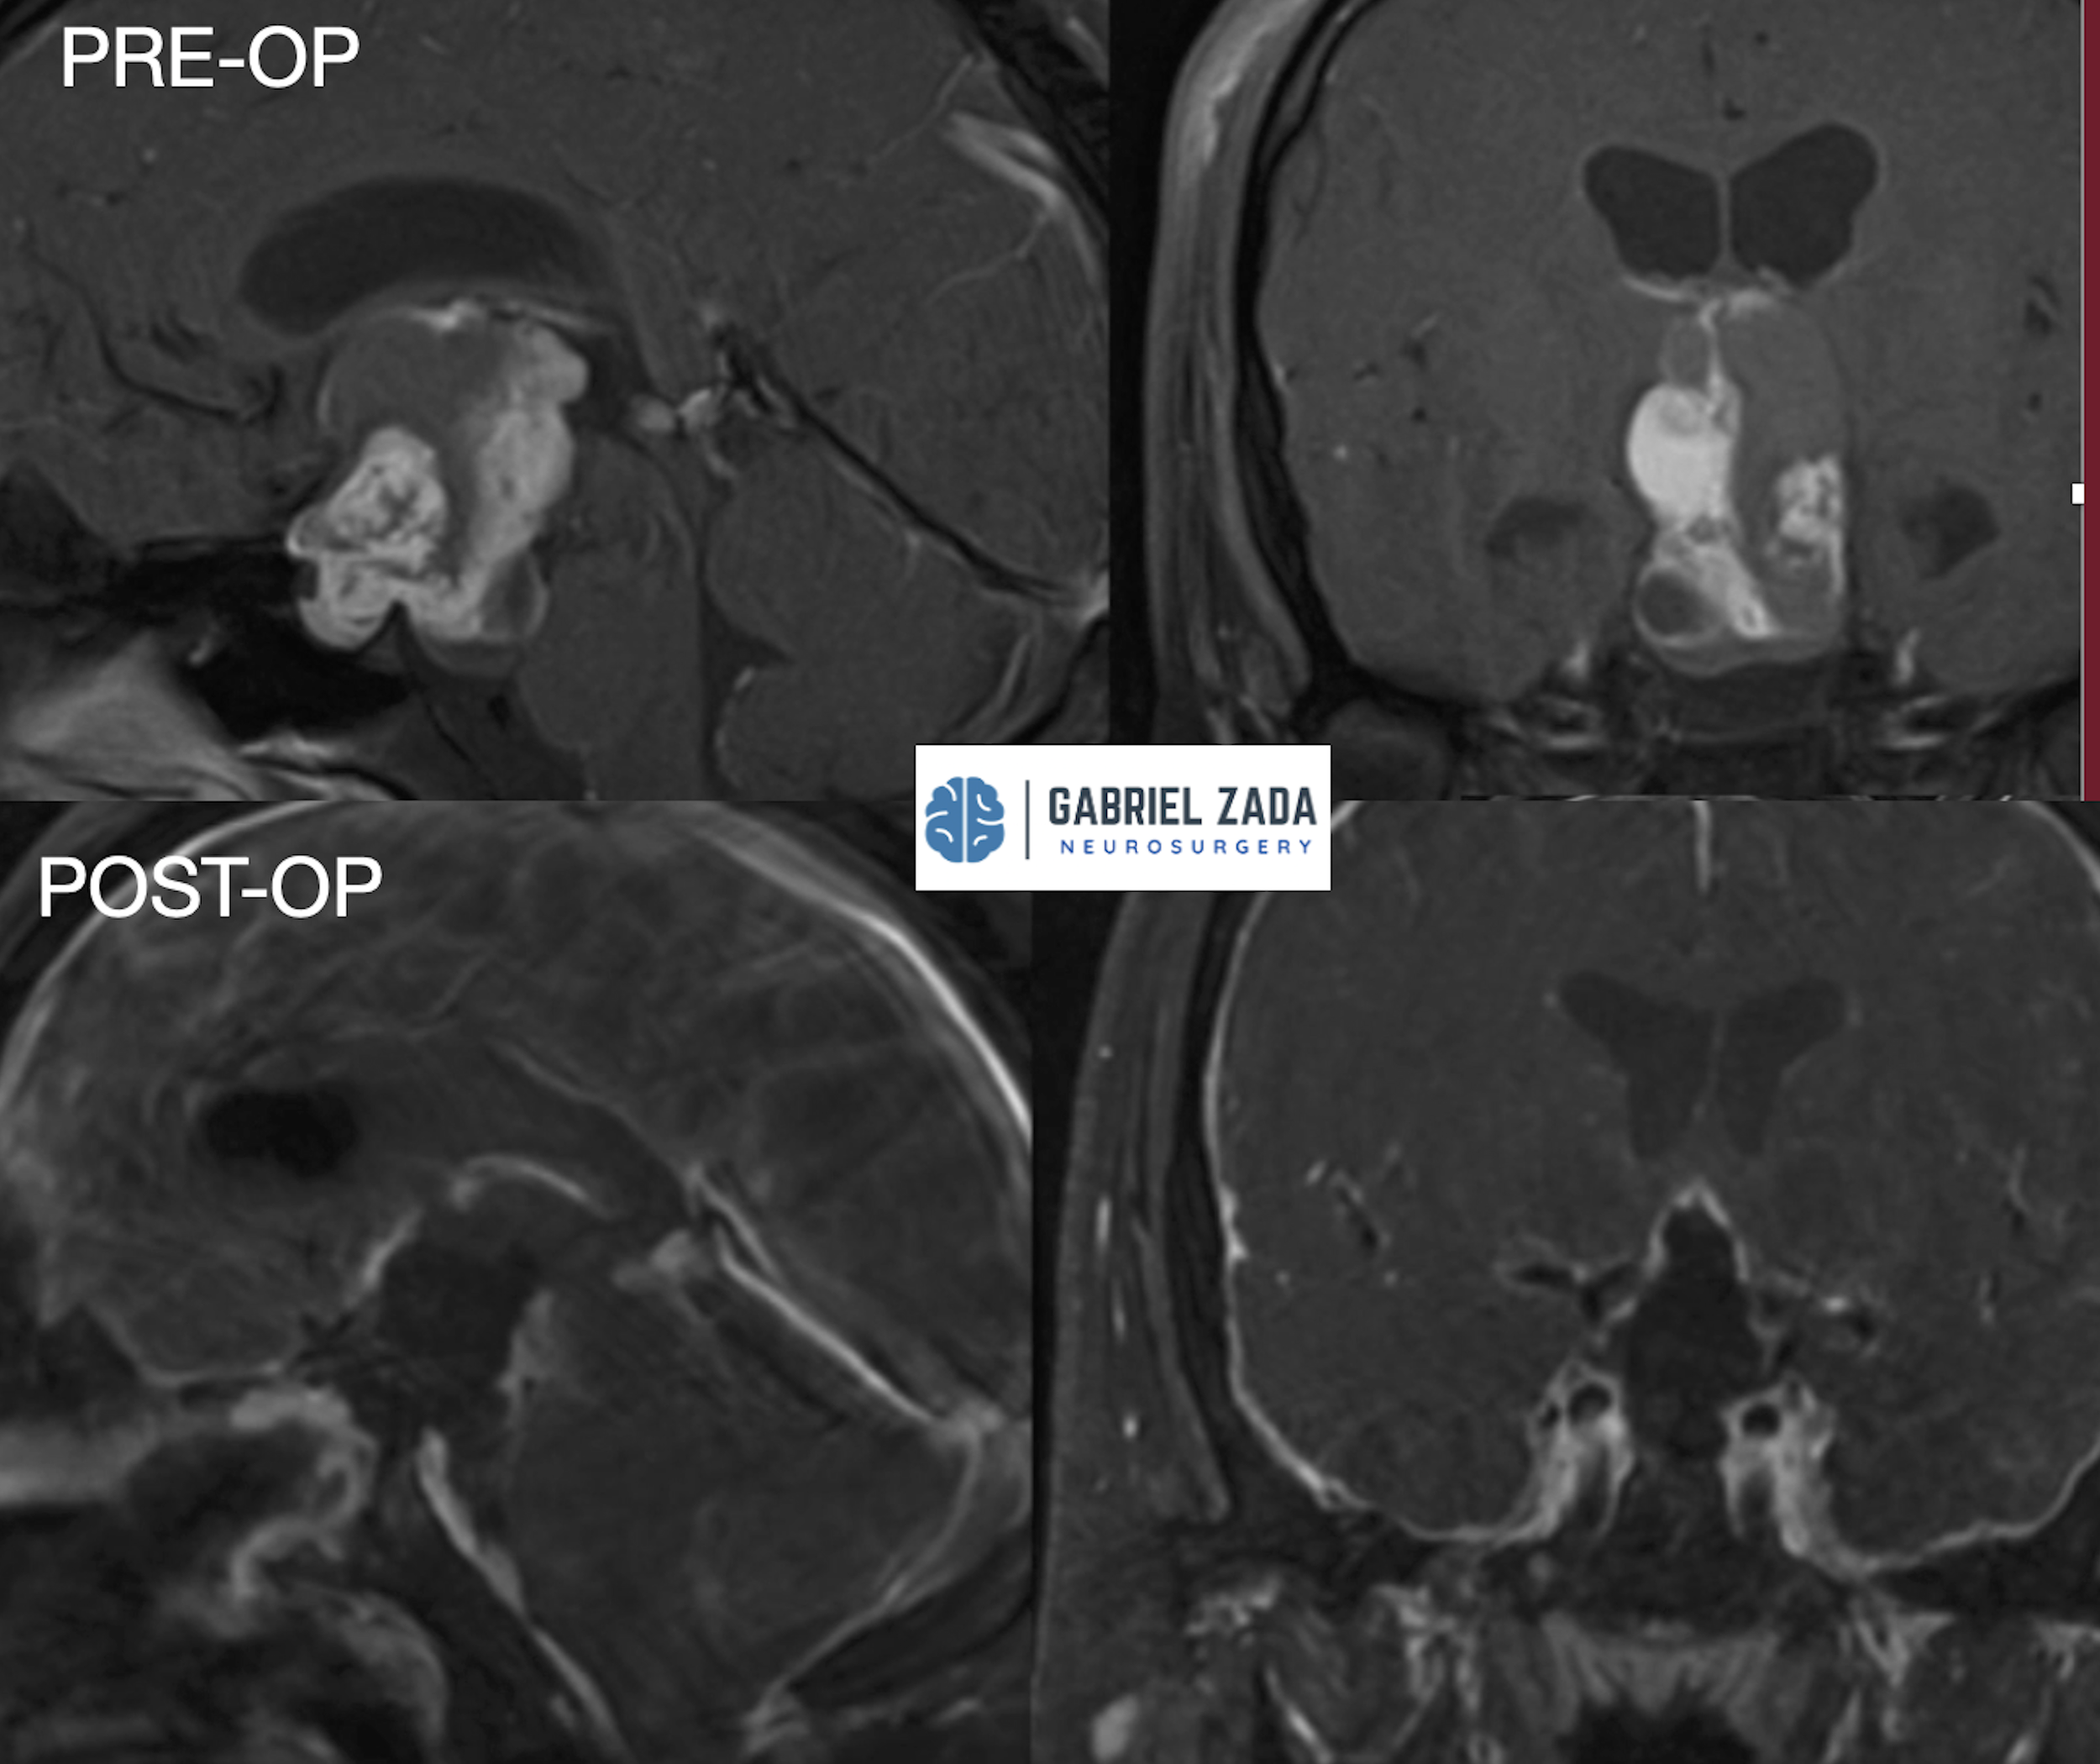

Explore this comprehensive gallery featuring pre‑ and post‑operative imaging of patients with skull‑base tumors treated by Gabriel Zada, MD, MS, FAANS, FACS. These cases highlight Dr. Zada’s expertise in advanced neurosurgical techniques and outcomes.

*Representative cases shown for educational purposes. All images de-identified. Individual results vary.